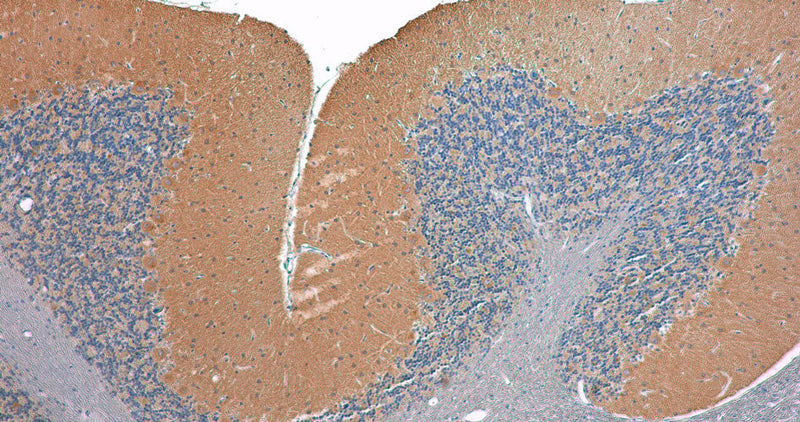

Representative image of formalin fixed paraffin embedded section

of rat cerebellum section stained with Aves Labs anti-Cavα2δ2 recombinant chicken monoclonal antibody (brown, Cat No. 78-530) and counterstained with hematoxylin (blue). Anti-Cavα2δ2 specifically stains the Purkinje cells in the cerebellum.